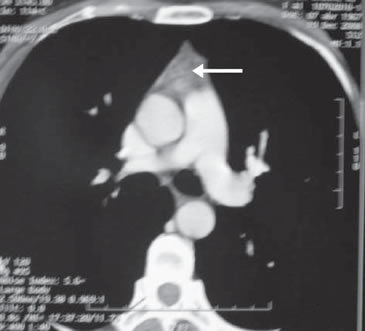

Se inició tratamiento con L-tiroxina (Eutirox®) en dosis ascendentes hasta llegar a 150 mcg/d (TSH: 0,06 uUI/mL). Al completar un año de operada, la ecografía cervical fue totalmente negativa, pero la Tg estimulada fue 8,7 ng/mL (TSH: 64 uUI/mL) con negatividad de los Ac anti Tg. Después de una segunda dosis de 100 mCi de I131, el rastreo sistémico sólo mostró un leve aumento en la captación de I131 en línea media baja, en situación retro esternal (Figura 2). El hallazgo descrito correspondía a captación mediastínica. En el control a los 18 meses, la Tg (sin estímulo) era indetectable (< 0,5 ng/mL), persistiendo la negatividad de los Ac anti Tg. Al completar el segundo año de seguimiento, la ecografía cervical no mostró ningún hallazgo patológico. Dado el antecedente de captación cervical baja, se solicitó un TAC cervical y torácico que mostró un lecho tiroideo libre y ausencia de adenopatías; en el mediastino superior, se describe una imagen triangular en el espacio prevascular, que se interpretó como persistencia del timo (Figura 3).

Figura 3. Tomografía computada de tórax mostrando la presencia de timo.

Este caso ejemplifica como, en situaciones como la descrita, se está proclive a interpretar la captación cervical anterior baja del isótopo como parte de la enfermedad tumoral, más aún si el genio biológico del tumor es agresivo, como sucedió en nuestra paciente, y asociado a Tg positiva (8 ng/mL). Sin embargo, en el control efectuado a los dos años de la cirugía, y habiendo recibido dos dosis de yodo radioactivo, la ausencia de hallazgos ecográficos, y la negatividad de la tiroglobulina, pero con persistencia de la captación mediastínica alta de I131, hizo plantear una causa espuria de esa captación, siendo la primera de ellas la persistencia del timo. Las imágenes del TAC confirman esa hipótesis diagnóstica (Figura 3).